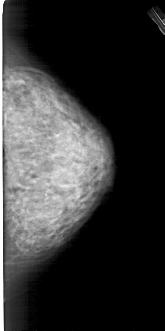

ics_version 1.0 filename A-1282-1 DATE_OF_STUDY 7 8 1995 PATIENT_AGE 54 FILM FILM_TYPE REGULAR DENSITY 4 DATE_DIGITIZED 7 7 1998 DIGITIZER HOWTEK 43.5 SEQUENCE LEFT_CC LINES 5266 PIXELS_PER_LINE 2761 BITS_PER_PIXEL 12 RESOLUTION 43.5 OVERLAY LEFT_MLO LINES 5491 PIXELS_PER_LINE 2971 BITS_PER_PIXEL 12 RESOLUTION 43.5 OVERLAY RIGHT_CC LINES 4951 PIXELS_PER_LINE 2461 BITS_PER_PIXEL 12 RESOLUTION 43.5 NON_OVERLAY RIGHT_MLO LINES 5446 PIXELS_PER_LINE 2776 BITS_PER_PIXEL 12 RESOLUTION 43.5 NON_OVERLAY |